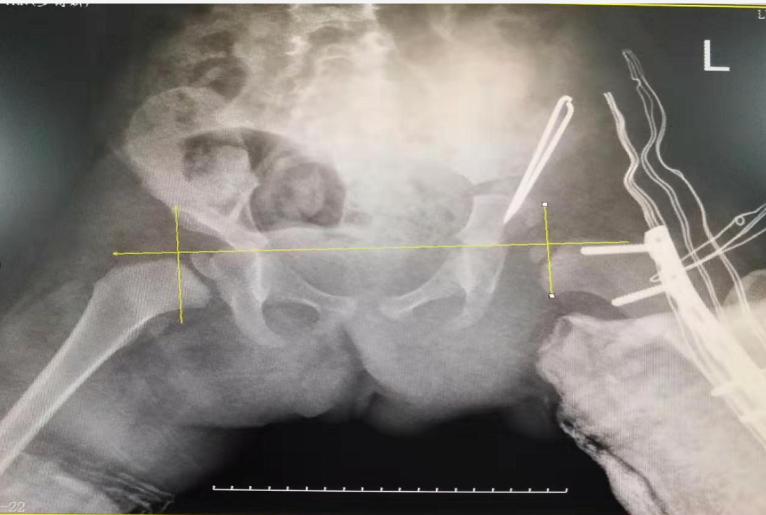

2歲零1個(gè)月的幼兒玥玥(化名)因先天性髖關(guān)節(jié)脫位(也就是我們常說(shuō)的“長(zhǎng)短腿”)來(lái)到了瀘州市中醫(yī)院治療。在醫(yī)院骨傷三科岐黃名中醫(yī)、副主任中醫(yī)師鄭磊的帶領(lǐng)下,科室與麻醉科密切配合,順利為玥玥實(shí)施了手術(shù)。

術(shù)前

術(shù)后

據(jù)了解,玥玥的左腿比右腿要短3厘米,導(dǎo)致她走起路來(lái)“不對(duì)頭”:一拐一拐的,像小鴨子走路一樣。